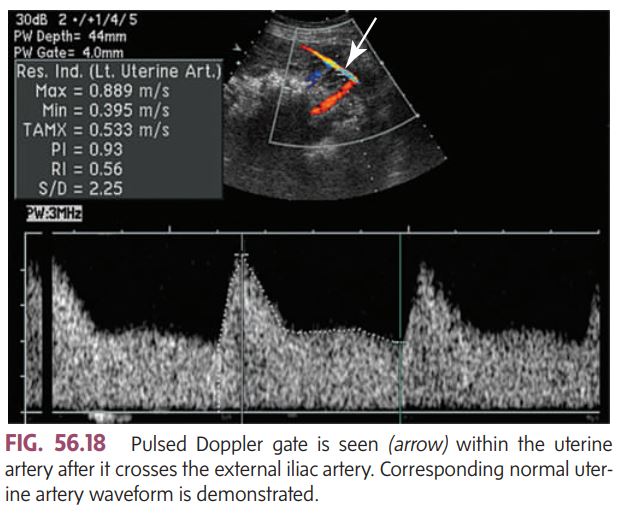

The uterine arteries are the main blood supply to the placenta.

By assessing them with color Doppler, we can see if enough oxygen and nutrients are reaching the placenta and fetus.

It helps detect problems like placental insufficiency (when the placenta isn’t getting enough blood), which can lead to fetal growth restriction or preeclampsia.

In a healthy pregnancy, the __________ shows _____ (good continuous flow throughout diastole), meaning the placenta is well perfused and active.

If there’s high resistance or notching in the waveform, it can suggest poor placental development or function.

normal placenta: uterine artery shows low-resistance flow